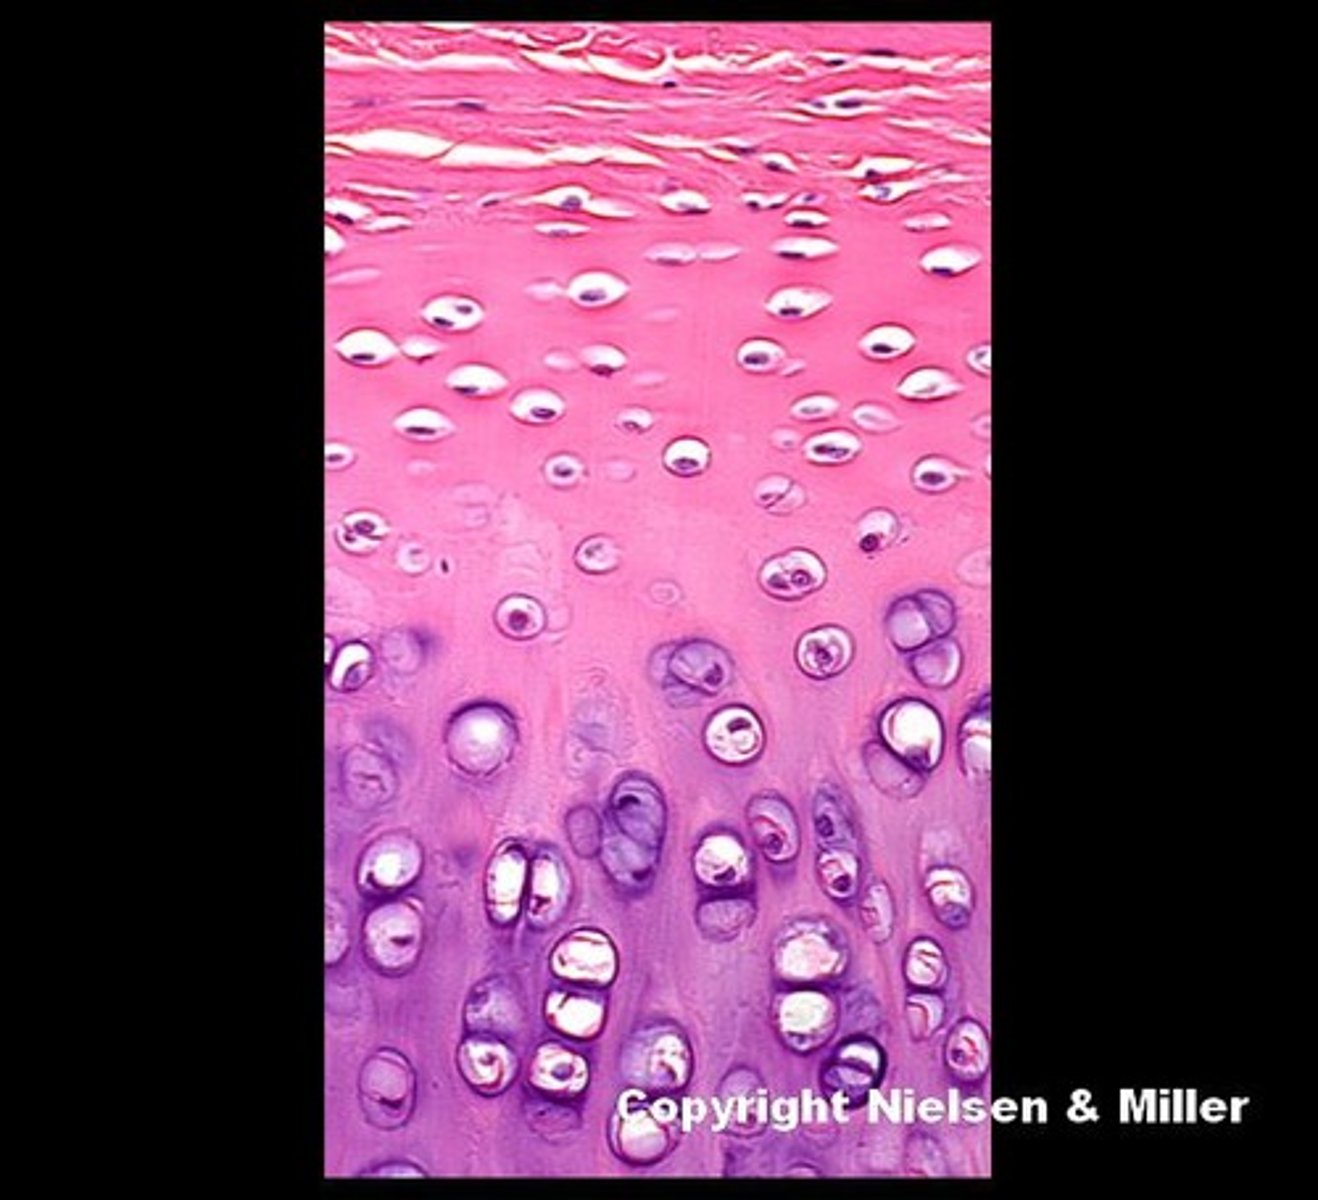

pseudostratified columnar epithelium